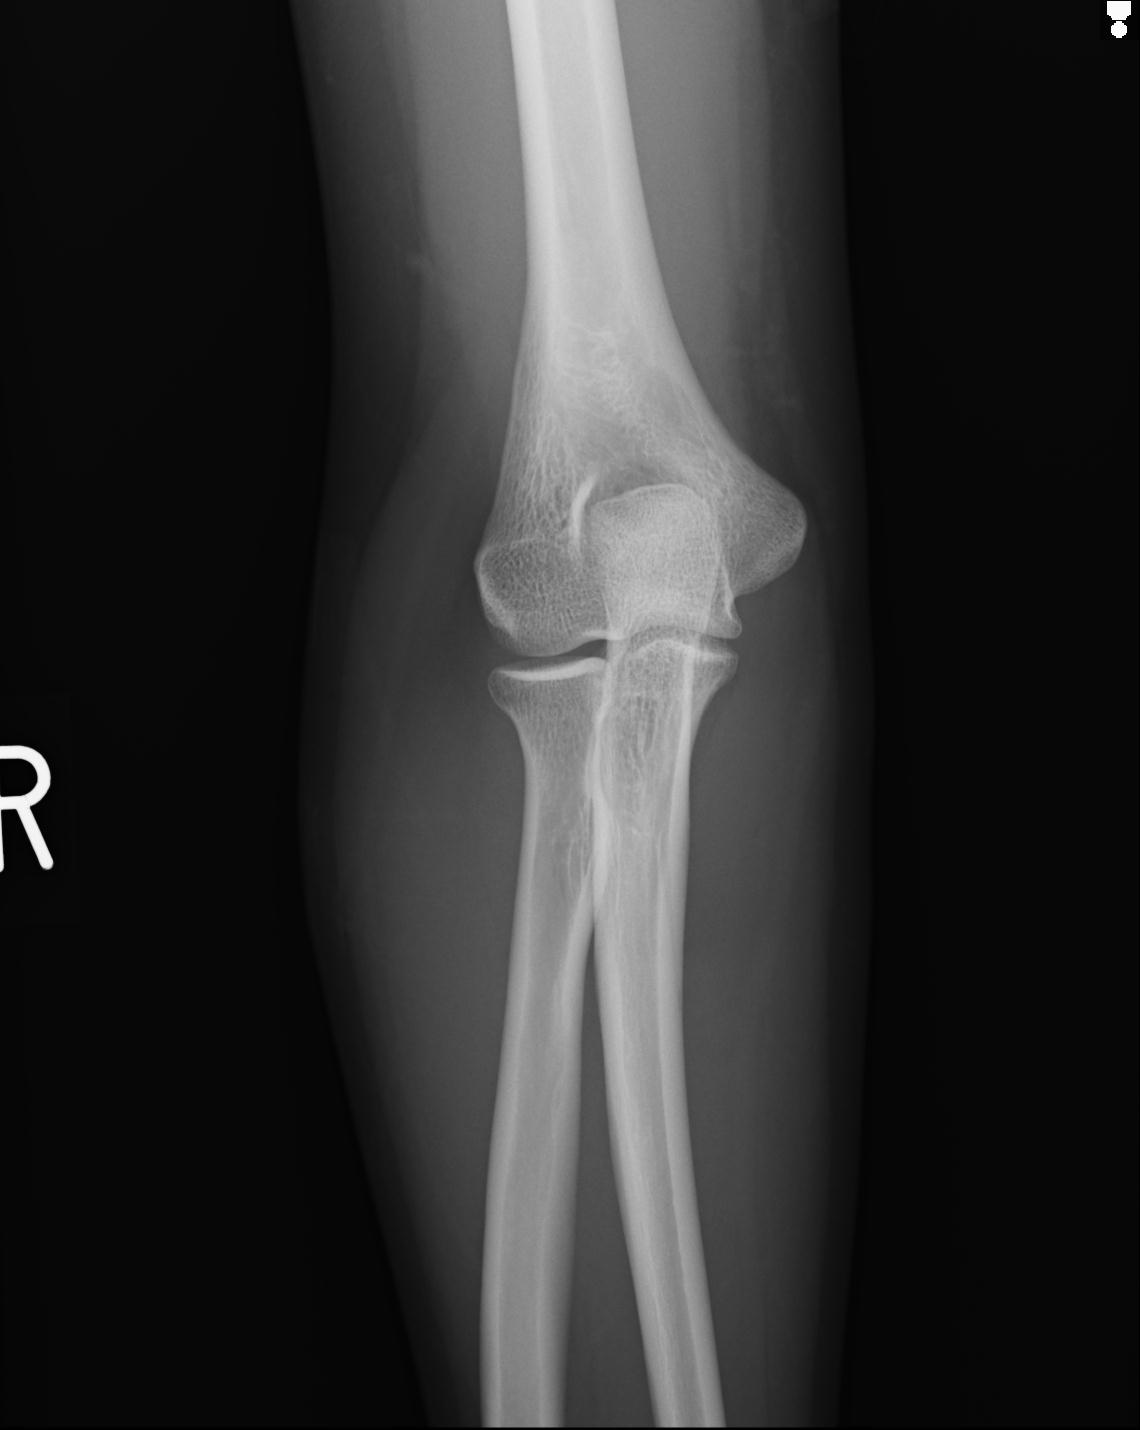

2271 1/25 右肘 4R 1/27 4R 3/24 4R 94歳女性 右通顆骨折